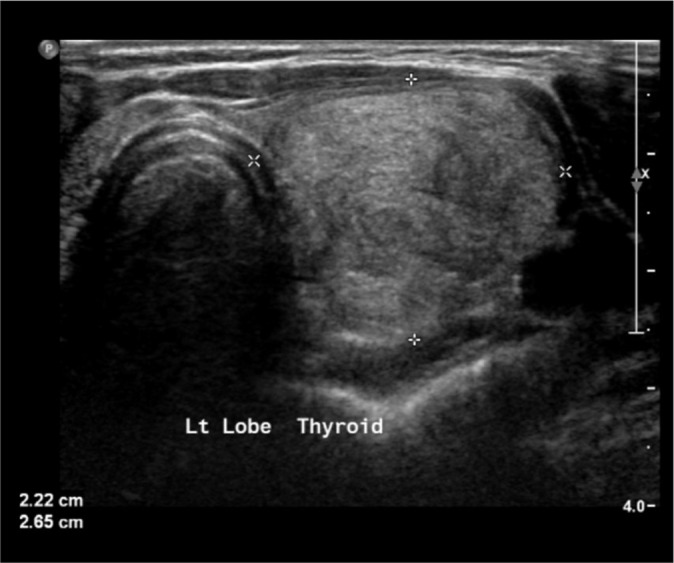

Objective: Thyroid nodules are frequently encountered in medical practice. Fine needle aspiration cytology (FNAC) is used to rule out malignant nodules, but few studies have questioned the accuracy of FNAC in larger thyroid nodules compared to smaller ones. We, therefore, aim to compare the diagnostic performance of FNAC based on nodule size and whether larger nodule size increases the possibility of obtaining indeterminate or non-diagnostic results.

Material and methods: Adult patients with thyroid nodules who underwent thyroid biopsy and surgery from 2016 to 2022 were included in the study. We assessed the proportion of benign, malignant, indeterminate, and non-diagnostic FNAC in relation to the nodule size. We then divided cytology into true positive (malignant FNAC and histology), and true negative (benign FNAC and histology) and examined whether the proportion of true FNAC would be affected by different thyroid nodule cutoffs. The study used mean and frequency to describe continuous and categorical variables. t-test and Chi-square tests were used to compare statistics.

Results: Three hundred and forty-five patients were included in the study. The majority were female (86.7%) and older than 40 years. Half had a benign histology; the other 50% were malignant. The majority (49.3%) had indeterminate thyroid cytology. The proportion of indeterminate or non-diagnostic FNAC was the same (58%) in nodules ≥4 cm and <4 cm. The proportion of true FNAC was similar between different nodule size categories. It was 35% in ≥4 cm, and 34.3% in <4 cm nodules.

Conclusion: The study found that the diagnostic performance of FNAC in thyroid nodules did not significantly differ based on nodule size, with similar rates of indeterminate or non-diagnostic results across different size categories. The proportion of true positive FNAC results also remained consistent regardless of nodule size.